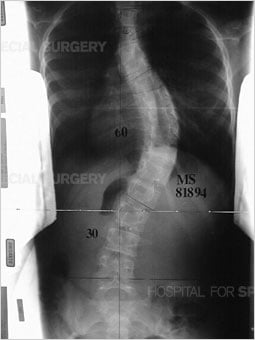

Adolescent idiopathic scoliosis a condition in which the spine is curved sideways in one or more areas [Figure 1], with no known cause. This different from that in the condition known as kyphosis, where the spine has an abnormal, forward-oriented curvature [Figure 2]. It affects girls more frequently than boys.

Figure 1: Anteroposterior (front to back) view of the spine (standing) demonstrates scoliosis in the thoracic and lumbar spine. |

To assess the curve further, X-ray images or low-dose radiation EOS images are taken from the front and side views [Figures 4, 5]. Side-bending X-rays may also be taken to assess the flexibility of the curve or curves. Sometimes these images reveal two curves: the first curve to appear in the spine (the primary curve) and the compensatory curve that the patient develops through his or her effort to maintain an erect posture.

Figures 4 (left) & 5 (right): Anterior to posterior (front to back) and lateral

(side) X-rays showing a scoliosis curve from the back and side, respectively.